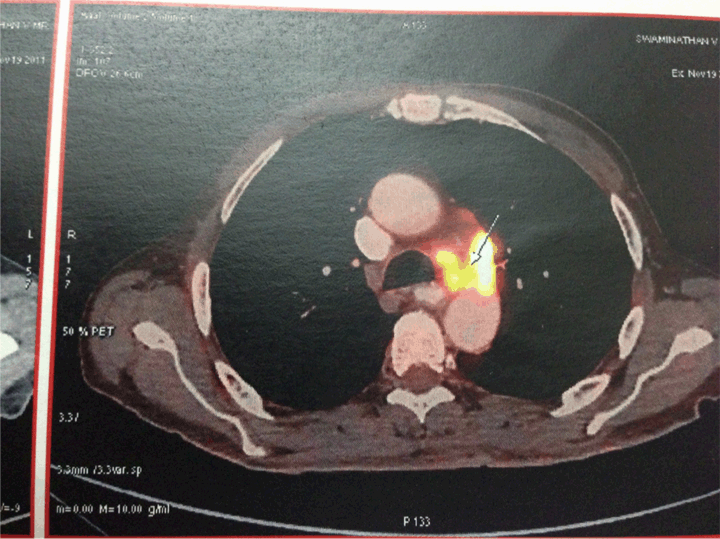

A 72-year old male, without any known comorbidities, was admitted to our hospital due to altered mental status, weakness, anorexia, hematemesis and urinary incontinence for three days. He complained of abdominal distension and dyspepsia for the last two years. There was a loss of appetite and weight of about 10 kg. At the time of admission to hospital, physical examination revealed blood pressure 110/80 mmHg, tachycardia 120 bpm with no other specific systemic finding. The patient was severely dehydrated, presented with decreased reflexes and his skin showed hyperpigmentation. (Figure 1) Laboratory tests demonstrated hyponatremia (serum sodium 125 mEq/L), hyperkalemia (serum potassium 5.6 mEq/L), anemia (Hb 7.3 g/dL) and mild metabolic acidosis (pH 7.25). The electrocardiogram showed normal QRS complexes. There was a mild rise in serum urea 47 mg/dL and normal serum creatinine levels 0.8 mg/dL. After ruling out tuberculosis and drug induced adrenalitis, computed tomography (CT) scan of chest and abdominal was done. Gastric carcinoma with perigastric, periceliac and para aortic lymphadenopathy along with bilateral metastases of the adrenal glands was found. (Figure 2) We performed a whole body positron emission tomography (PET) scan which further validated the CT findings. (Figure 3) The biopsy showed a moderate to poorly differentiating adenocarcinoma in the gastric antrum. Based on the patient’s clinical status and the laboratory test results, in addition to the magnitude of the adrenal masses, we decided to perform a high dose cosyntropin stimulation test. The serum cortisol level was 420 nmol/L before the intramuscular administration of cosyntropin (250 µg), and 61,438 nmol/L 60 minutes after the administration. These results combined with the elevated levels of adrenocorticotropic hormones (ACTH) 165.7 pg/mL before the administration, and the diagnosis of adrenal insufficiency had been established.

Figure 2: Computed tomography scan of abdomen.